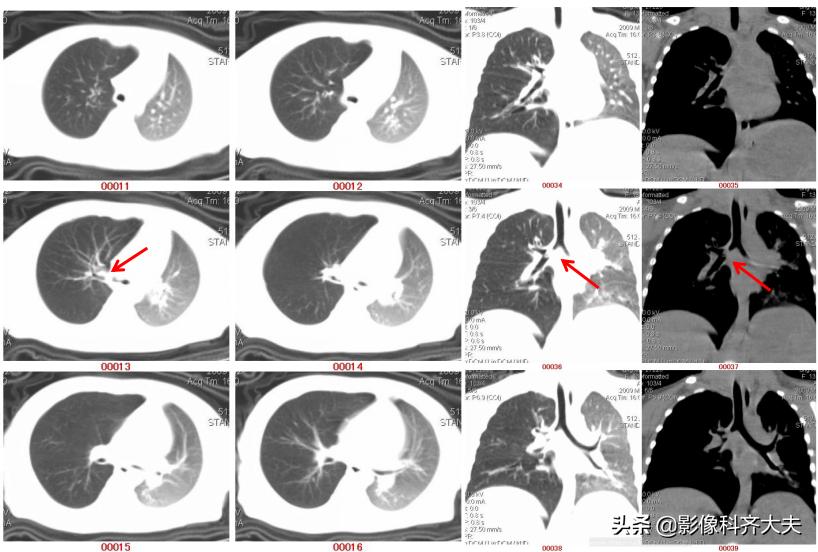

病例1、病史:患儿,女,一岁半,咳喘两周,病前有“开心果”吸入史。

图为轴位及冠状位重建图显示异物:红色箭头为异物的位置,冠状位显示尤为清晰。